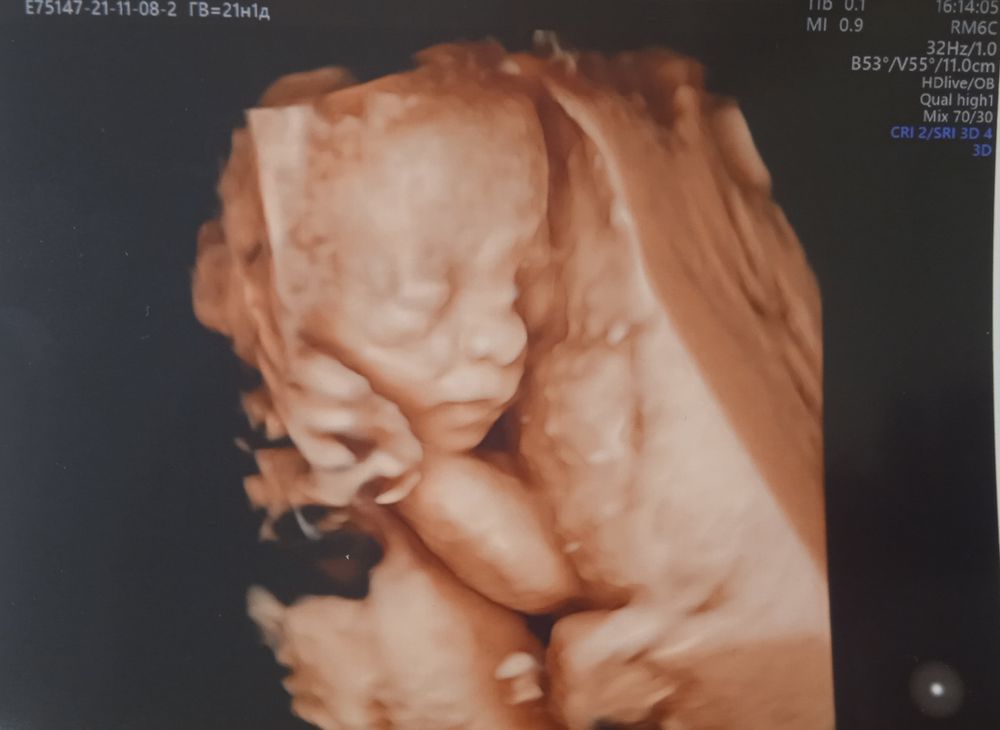

21 неделька, вроде не устрашающе выглядит всё,как ниже написали🙈😉